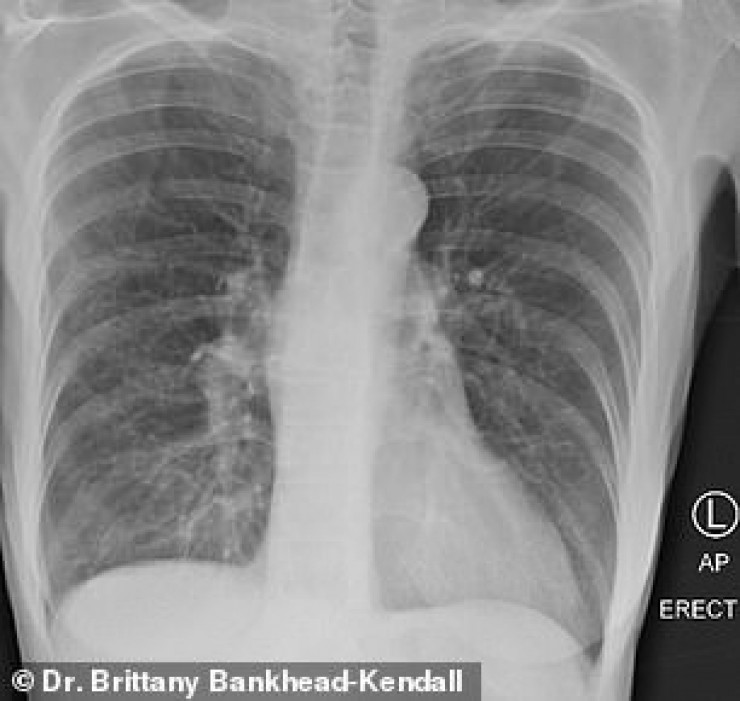

У курильщика они частично побелели от рубцов, и снимок выглядит слегка туманным.